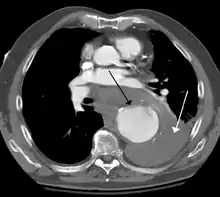

A thoracic aortic aneurysm is an aortic aneurysm that presents primarily in the thorax.

A thoracic aortic aneurysm is the "ballooning" of the upper aspect of the aorta, above the diaphragm. Untreated or unrecognized they can be fatal due to dissection or "popping" of the aneurysm leading to nearly instant death. Thoracic aneurysms are less common than an abdominal aortic aneurysm.[2] However, a syphilitic aneurysm is more likely to be a thoracic aortic aneurysm than an abdominal aortic aneurysm. This condition is commonly treated via a specialized multidisciplinary approach with both vascular surgeons and cardiac surgeons.

The principal causes of death due to thoracic aneurysmal disease are dissection and rupture. Once rupture occurs, the mortality rate is 50–80%. Most deaths in patients with Marfan syndrome are the result of aortic disease.